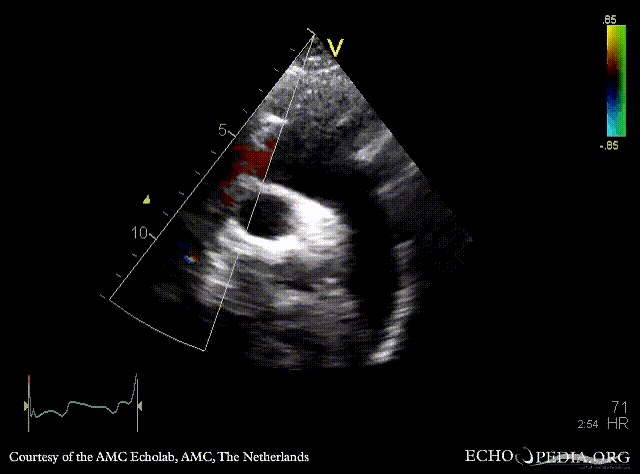

PLAX: subvalvular membrane in left ventricle outflow tract PLAX with Color Doppler: high velocity flow in left ventricle outflow tract